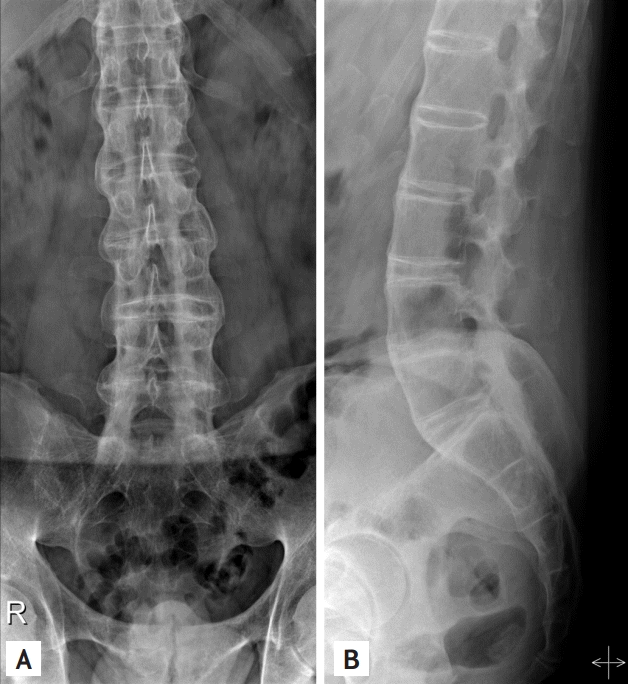

A 34-year-old man presented with crops of pustules with erythematous scaly patches on his soles and palms (Fig. 1A-1D). Both great fingernails showed trachyonychia and onycholysis with transverse ridges (Fig. 1E). He had a 6-year history of ankylosing spondylitis manifested as positive human leukocyte antigen B27 (HLA-B27) and bilateral sacroiliitis. In the radiographs taken 8 months prior to presentation, his sacroiliac joints were fused, and a bamboo spine was seen (Fig. 2). As his back pain did not improve despite the use of both nonsteroidal anti-inflammatory drugs and sulfasalazine over 8 months, adalimumab was started 3 months prior to presentation. Histopathologic examination revealed hy-a perkeratosis, parakeratosis, and a pustule in the corneal layer and spongiosis and perivascular lymphocytic infiltration in the upper dermis, consistent with psoriasiform dermatitis (Fig. 1F). Palmoplantar pustulosis secondary to adalimumab was suspected. After discontinuing the adalimumab, the skin lesions improved with topical corticosteroid and calcipotriol ointment. Two months later, etanercept was administered to control a flare of ankylosing spondylitis, and no recurrence has been noted for 2 years. Anti-tumor necrosis factor (TNF) agents are widely used in the management of various inflammatory disorders, including inflammatory bowel disease, rheumatoid arthritis, and ankylosing spondylitis. Growing numbers of clinical observations have described the paradoxical incidence or exacerbation of psoriasis in patients treated with anti-TNF agents, although the agents are also effective for psoriasis itself. Unopposed activation of the interferon-α pathway following neutralization of TNF has been suggested as the possible mechanism. A class effect is proposed for this paradoxical event, but other anti-TNF agents could be cautiously tried because the magnitude of the effect across anti-TNF agents could be different.

Figure 2.

Plain lumbar radiograph of the patient shows bamboo spine and complete fusion of sacroiliac joints. (A) Anteroposterior view, (B) lateral view